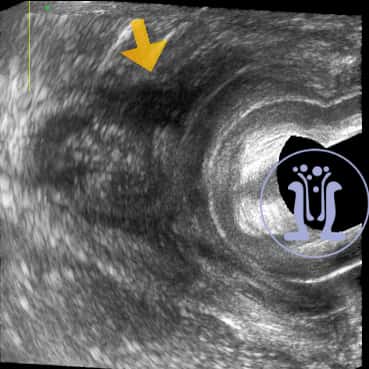

Γυναίκα ασθενής 31 ετών προσέρχεται με φλεγμονή στο δεξί μεγάλο χείλος του αιδοίου από μηνός. Στο ιστορικό της αναφέρει εγχείρηση για βαρθολίνειο δεξιά προ διετίας. Κλινικά ανευρίκεται δερματικό στόμιο δεξιά κοντά στο κόλπο και η εξετάστική μήλη διεισδύει σε ενα μεγάλο βάθος. Υπερηχοτομογραφικά ανευρίσκεται επικοινωνία με το έντερο που συμπεριλαμβάνει όλο το μήκος του σφιγκτήρα στην 12η ώρα.